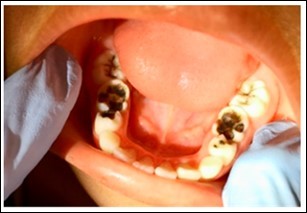

Figure 3.Example intraoral image of arrested cavitated caries lesions ost treatment.

Although these three humanitarian community outreach programs were not conducted as research, and should be looked at as separate case reports, careful attention to data collection was made at initial examination and at all follow up encounters. The Shoreview Dental, LLC team exclusively conducted data analysis on outcomes data related to Ecuador and Ghana but collaborated with the Smiles Forever Foundation for data analysis related to Bolivia. Surface specific charting and maxillary and mandibular arch photos were taken at all timepoints in Ecuador and Ghana but only at 36 months in Bolivia. A determination of all cavitated caries lesion activity or arrest was recorded based on lesion color and surface hardness. A lesion was considered arrested if the color was black and the surface was determined to be hard using gentle tactile examination (Figure 3).12,15 The presence or absence of caries lesion related mouth pain was asked of the children themselves as well as their parents and teachers.

The results discussed below are derived from Table 1. Please review the table for a more comprehensive evaluation of outcomes. Pre-treatment intraoral image examples of cavitated caries lesions in Ecuador, Ghana and Bolivia can be found in Figure 2. An example of arrested cavitated caries lesions can be found in Figure 3. All charted information for all patients was stored securely and confidentially and data was anonymized before evaluation of outcomes.